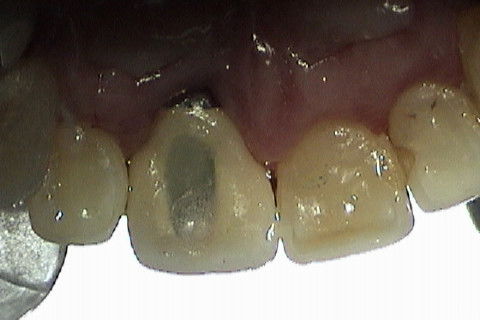

Caso clínico de Implantodontia     Há 14 anos

Paciente com fratura do elemento 11. Como havia grande perda óssea vestibular, optamos por fazer implante primeiramente a extração do dente e após 4 meses a colocação do implante. Concomitante 'a colocação do implante, enxerto óssseo + membrana para regeneração óssea foi colocado e aguardamos 6 meses para então fazermos a reabilitação com coroa metalo-ceramica parafusada.